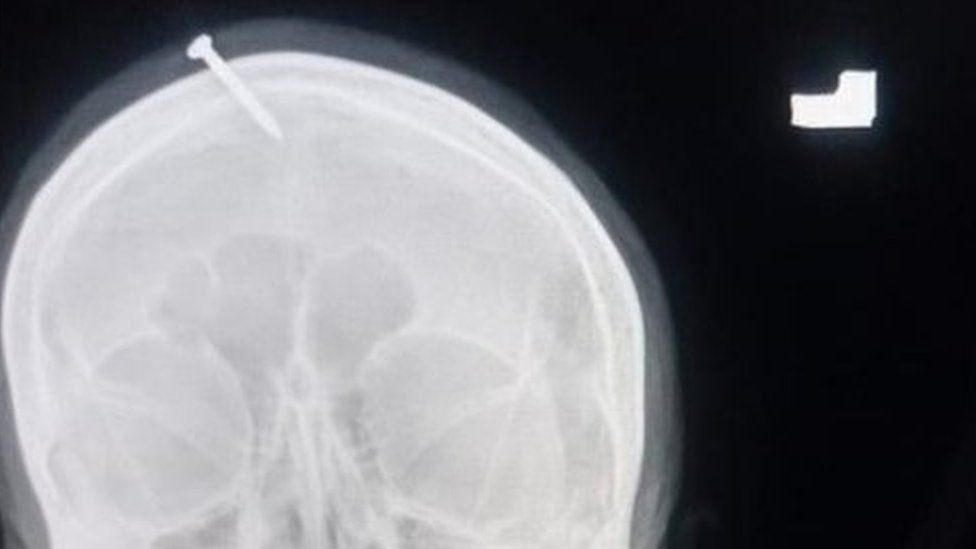

තමාට ඇති බලයෙන් පිරිමි දරුවෙකු ලබාදීමට හැකි බවට පැවසූ මිත්‍යා ඇදහිලි සුවකරන්නෙකු ගේ කීමට අනුව සිය හිසට ඇණ ගසා ගත් ගර්භණි කාන්තාවක් සම්බන්ධයෙන් පුවතක් පාකිස්ථානයෙන් වාර්තා වනවා.